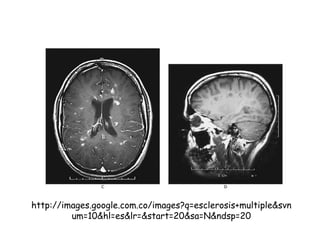

MIELINA-MIELINIZACIÒN La mielinaes la base estructural de la teoría saltatoria del impulso nervioso El segmento de revestimiento forma el internodo de Ranvier, el espacio entre dos de estos internodos es el nodo de Ranvier (sitio de regeneración del impulso nervioso). Existen varios tipos de enfermedades desmielinizantes Afectan a los oligodendrocitos y a la mielina no al axon a. Autoinmunes Esclerosis múltiple-Guillan Barre b. Hereditarias adrenoleucodistrofia, ligada al X, en el suero ácidos grasos de cadena corta, daño en el gen que codifica las proteínas de los peroxisomas c. Metabólicas déficit de B12, mielinolisis pontina, en pacientes a quienes se les corrige hiponatremias por alcoholismo o por desnutrición d. Inducidas por virus encefalopatía focal progresiva, en el VIH sida los oligodendrocitos son invadidos por virus oportunistas e. Quimio-Rtpia

Diferencias entre lamielina del SNC y del SNP El SNP tiene mas esfingomielinas y glucoproteínas Proteína básica de la mielina, presente tanto en SNC como en SNP Proteína proteolipidica exclusiva del SNC Proteína cero de la mielina es la proteína mas importante del SNP Lamina basal en las Cels de Shwann importante para la regeneración nerviosa en el SNP Las fibras amielinicas son verdaderamente desnudas en el SNC Los nodos de Ranvier son mas grandes en el SNP, mas eficaz la teoría saltatoria del impulso nervioso